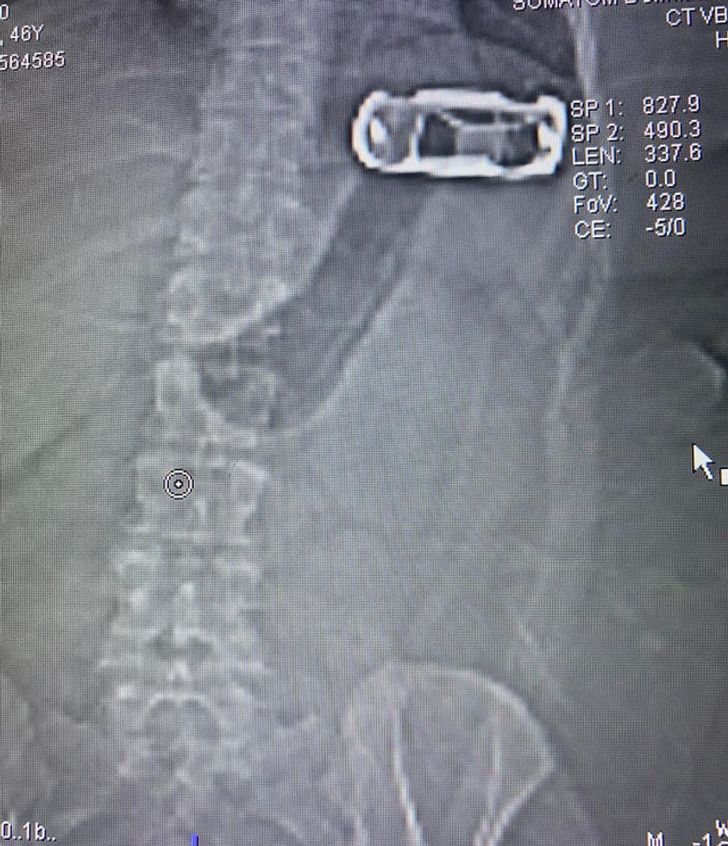

“Побачив знімок і подумав, що пацієнтка проковтнула машинку”

“У результаті з’ясувалося, що дівчина засунула в ліфчик іграшку для заспокоєння”.